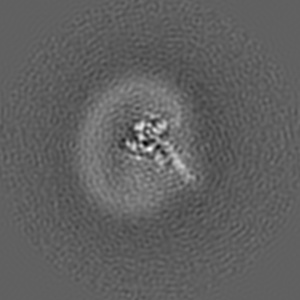

Cryo-EM structure of parathyroid hormone receptor type 1 in complex with a long-acting parathyroid hormone analog and G protein

Single-particle4.0 Å